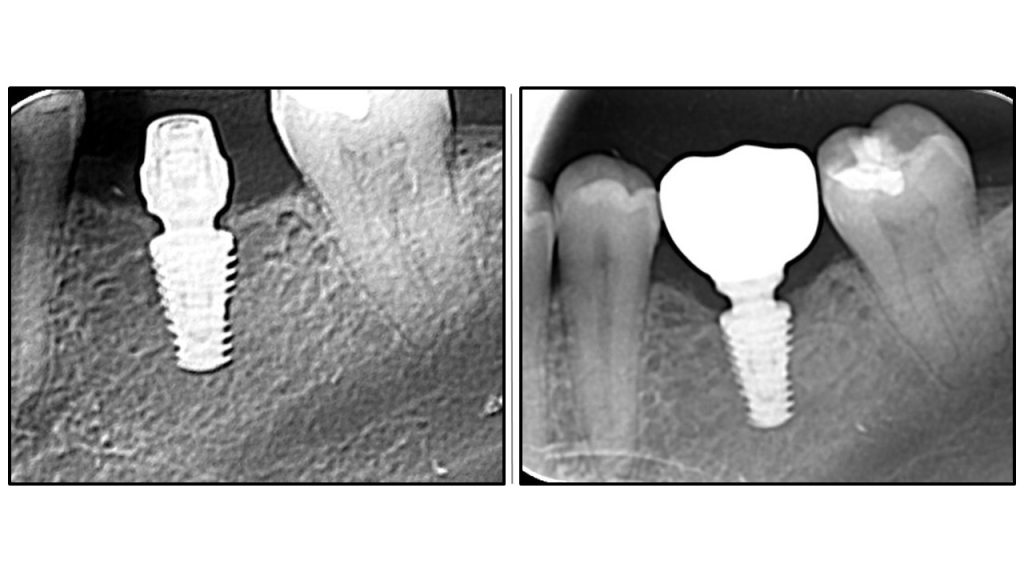

Радиографска анализа: стабилност костине крошне